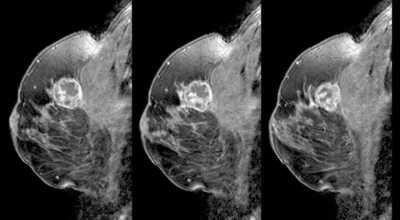

유방암 초기증상 - 유방의 혹

보통 응어리가 잡히는 분들의 40%는 물혹으로 가벼운 질병으로 바로 치유가 되는 경우가 많은데요 20~30%의 확률로 유방암일 가능성이 있다고 합니다. 따라서 매일같이 자신의 가슴을 마사지 해주시다 어느날 응어리가 잡히게 된다면 유방암 검사 초기에 받아 보시기를 권해 드려요.

초기에는 통증은 느껴지지 않습니다. 하지만 멍울이 만져질 수 있는데 손으로 느낄 만큼 멍울이 만져진다면 유방암 2기, 즉 초기증상일 확률이 높은데요 멍울이 가슴에 있기도 하지만 겨드랑이에서 만져지기도 합니다. 이런 증상이 나타난다면 바로 병원에 가서 검사를 받아보는 것이 좋아요.